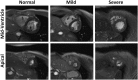

Pulmonary arterial hypertension (PAH) is characterized by elevated pulmonary artery pressure (PAP), altered pulmonary artery (PA) hemodynamics, and vessel wall characteristics that affect the right ventricular (RV) function. Magnetic resonance imaging (MRI) has recently been considered in PAH and has shown promising results for estimating PAP, measuring PA hemodynamic parameters, assessing PA vessel wall stiffness, and evaluating RV global and regional functions. In this article, we review various MRI techniques and image analysis methods for evaluating PAH, with an emphasis on the resulting images and how they are interpreted for both qualitatively and quantitatively assessing the PA and RV conditions.